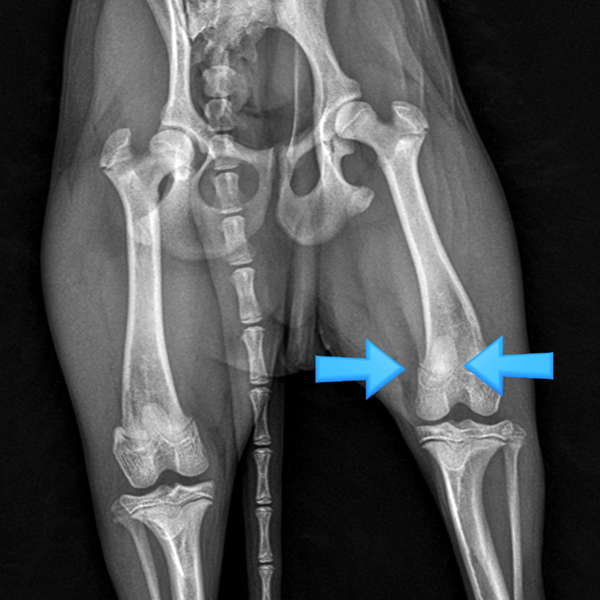

수술 전

(Before)

수술 후

(Afrer)